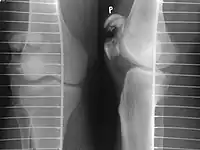

Vertical patella fracture